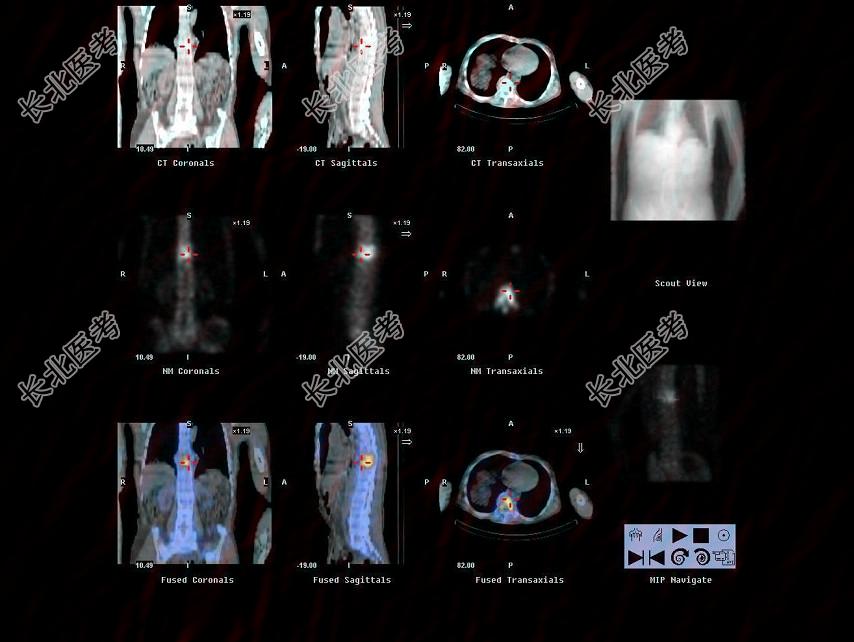

多项选择题男,68岁, 胸背痛3个月入院,行Tc-MDP全身骨显像、局部断层骨显像+X线图像融合如图, 可能的诊断是 ( )

A、多发性骨髓瘤

B、胸9、10椎体良性压缩性骨折

C、胸9、10椎弓根受累,提示恶性病变

D、大致正常的骨影像

E、胸9、10骨转移可能性大